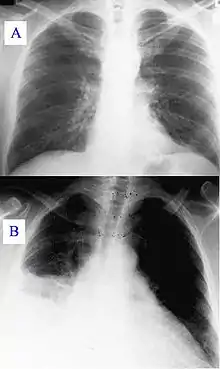

الحمى Q (بالإنجليزية: Q fever) مرض معدي ناجم عن الكوكسيلة البورنيتية، وهي بكتيريا تصيب الإنسان وحيوانات أخرى، من أبقار وغنم وماعز، وكذلك الكلاب والقطط. تحدث العدوى نتيجة استنشاق جسيمات غبار ملوثة بالبكتيريا المسببة، وكذلك بالتماس المباشر مع مفرزات الحيوانات المصابة من حليب وبول وبراز والمني والمفرزات المهبلية. تتراوح فترة الحضانة عادة بين 9 أيام و40 يوماً. تعتبر حمى Q من أكثر الأمراض عدوى، حيث تكفي بكتيريا واحدة لإحداث المرض عند البشر.[3]